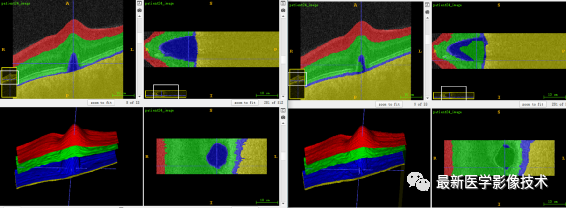

5、验证集分割结果

验证集平均结果

可以看到最大的错误发生在第 3 类(RPE 和 BM 之间的表面),导致错误分割的因素是显著的类别不平衡,如下所示。